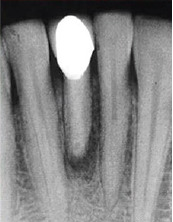

检查可见41牙大面积缺损,牙体变色,髓腔暴露,唇侧可见瘘道口。 X线片发现41牙根尖孔未完全形成,根尖周可见大面积低密度影,根中份可见有一高密度线性影像。仔细询问后发现患者有疼痛时往根管内放置尖锐物体的习惯。

诊断为41牙慢性根尖周脓肿。首先取出41牙根管内尖锐物体,其次完善根管治疗,进行根尖手术,控制根尖周炎症。

病例中患者幼时受到外伤后未及时诊治,而且在疼痛时往根管内放置尖锐物体,进而导致严重的根尖周炎症。由于根管内的异物能够通过疏通取出,故而未利用超声系统。患牙根尖孔尚未愈合,根管粗大,整个治疗过程中要尽量保存剩余牙体组织,修复时也选择与牙本质弹性模量相近的纤维桩进行修复。